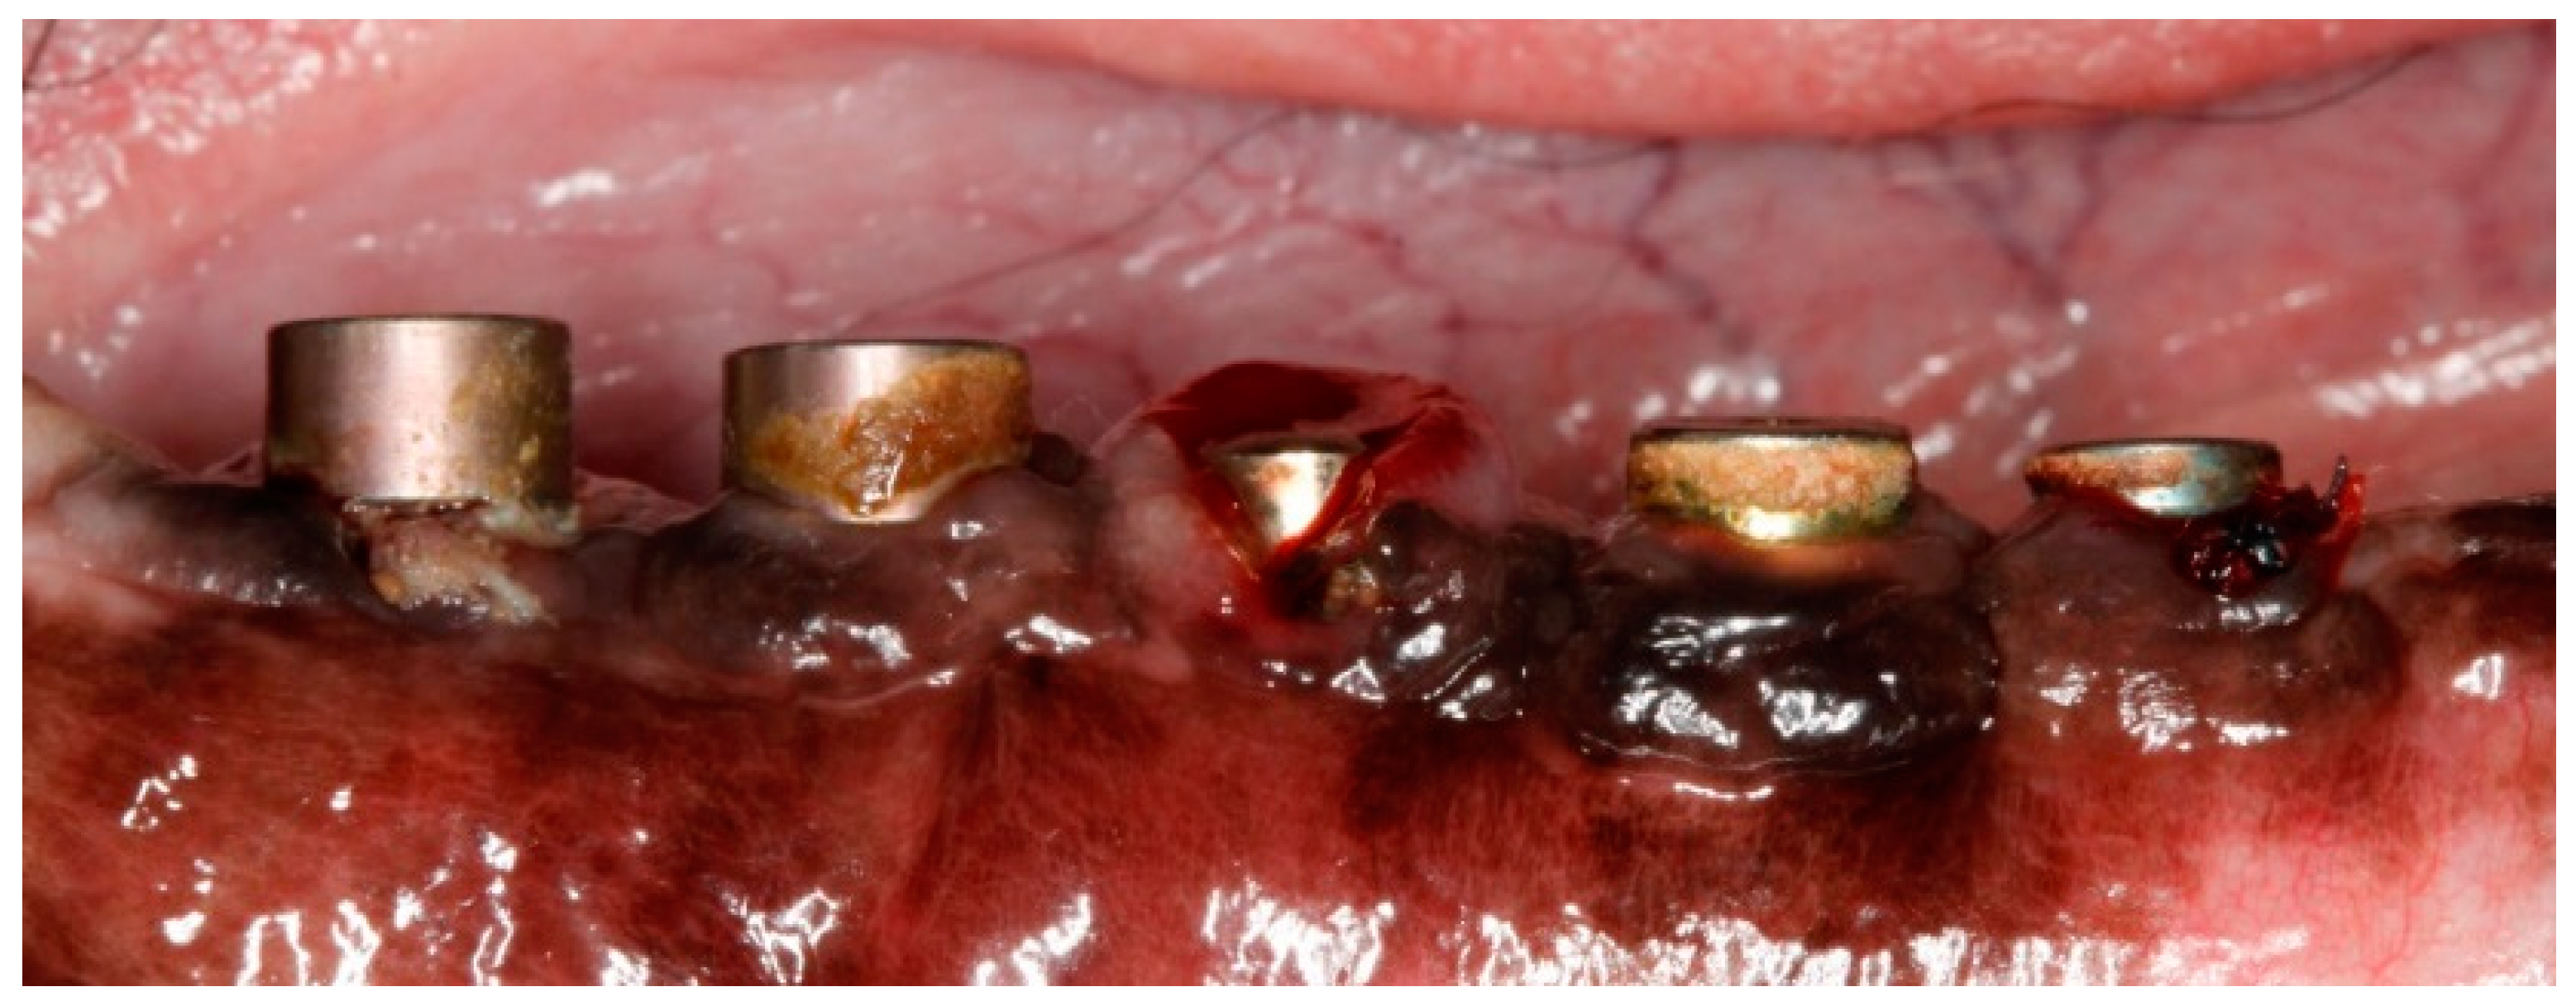

Figure 4. Post-operative image at 9-month post-implantation. Note the ligatures placed in alternating implants 1, 3 and 5, and the subsequent local inflammation.